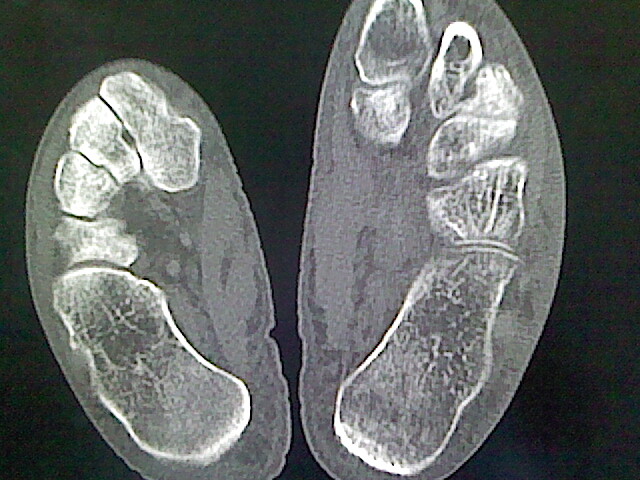

标题: CT16814:男,76岁,左小腿疼痛,不能站立 大家给看看 [打印本页]

男,76岁,左小腿疼痛,不能站立

本例骨质改变主要表现为滑膜或韧带区的骨侵蚀融解(胫腓联合区骨质破坏无硬化边),距骨后部骨质破坏区有硬化边及死骨样改变.所以,本例考虑关节结核可能性大,绒毛膜结节性滑膜炎多发于中年,且极少见于膝髋以外的关节,骨质硬坏也以压陷吸收为主,有明显的硬化边,骨膜增生呈结节状(可以mr鉴别),所以本例暂除外.

另不除外可引起相似表现的其他炎症如布氏杆菌性关节炎等